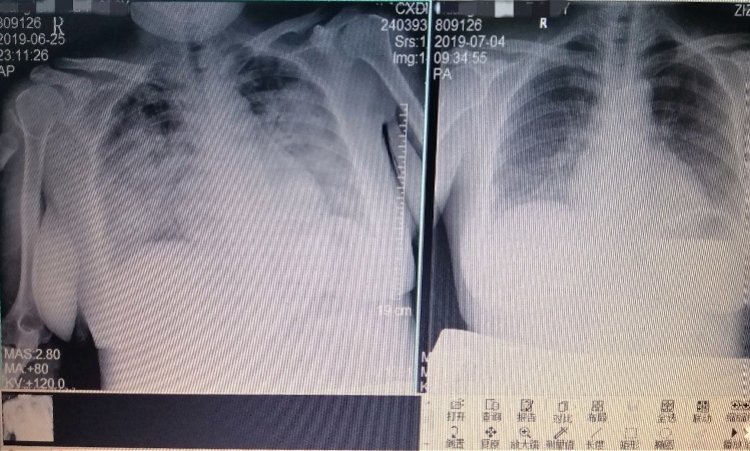

左:最为严重的时段,产妇已经变成了大白肺,呼吸濒临衰竭;右侧,经过系统的治疗应对后,病情缓解,肺部纹理开始出现。

更严重的是,影像检查结果显示,李女士已经开始出现“大白肺”。“肺部变白,意味着患者已经有严重的感染导致肺渗出,通俗点说就是吐纳气体的肺部,被浸泡在了水里。”王华副主任表示。